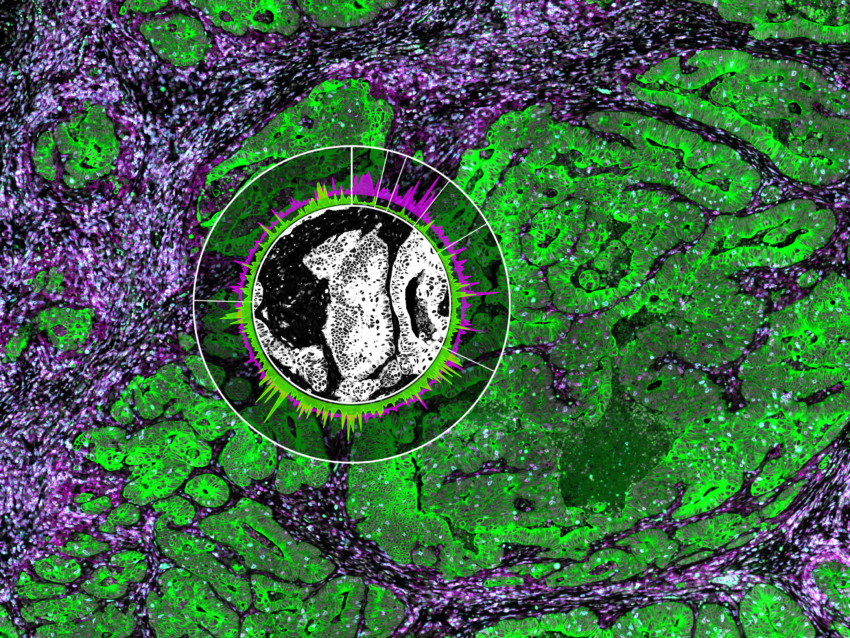

The immune microenvironment of ductal carcinoma in situ

Helga Bergholtz

Post-doctoral Researcher, Institute for Cancer Research, Oslo University Hospital